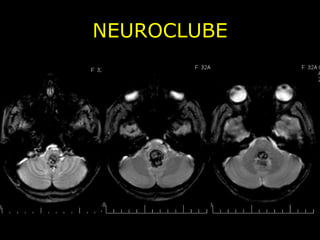

NEUROCLUBE